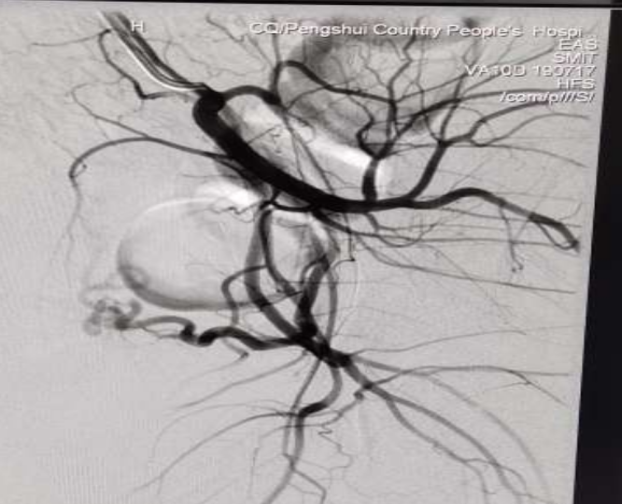

我院妇产科一位剖宫产瘢痕部位妊娠患者欲终止妊娠,彩超提示瘢痕妊娠部位血流丰富,如果直接行人流或者药流术,很容易引起大出血,存在切除子宫,甚至危及患者生命的可能。为了降低风险,经科内医生讨论后,决定为其先行子宫动脉栓塞术,再行清宫术。

26日上午10:50,妇产科医生欧春林在支医专家苏江利、孙会东,我院侯兴志、王启伦、廖洪梅和放射医生的协助下,成功完成子宫动脉栓塞术,上午11:50术毕安返病房。目前,术后患者恢复情况良好。

这是我院首例为患者做子宫动脉介入造影栓塞术,患者避免了更大创伤的手术治疗,避免了切除子宫的风险 ,争取了宝贵的治疗时间,同时还为患者节省了很多不必要的开支,更是填补了我院子宫动脉栓塞术的历史空白,具有划时代的意义。